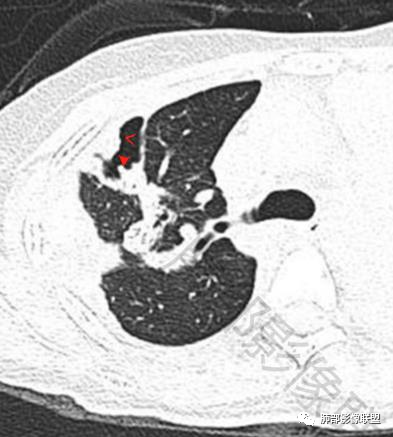

一切∮随缘:双侧胸廓塌陷,以右侧为主,右侧肋间隙狭窄,双肺上叶及右肺下叶胸膜下多发不规则肿块,密度不均匀,内部可见条片状,不规则钙化影,部分钙化不密实,双肺多发纤维索条影,似陈旧性病灶,双侧胸水,临床年轻女性,无感染症状,考虑考虑结核淀粉样变,转移性钙化,弥漫性肺骨化病。

王秀仙:双肺多发条索状及结节状病灶,部分钙化,边界清晰,双侧纵膈胸膜及双侧胸膜可见结块状及弧形软组织肿块,内见多发钙化灶,右侧胸腔塌陷,考虑结核伴淀粉样变性。鉴别胸膜间皮瘤。

丽:双肺散在索条及条片状高密度影,边界清晰,部分实变内可见钙化,支气管管壁增厚,双肺胸膜局限性增厚伴钙化,部分肋骨密度增高,首先考虑结核并淀粉样变性,鉴别转移性钙化,肿瘤样钙质沉着症,胸膜间皮瘤。

傅昌瑜:青年女性,咳嗽胸痛2月,偶有血痰。双肺上叶多发不规则肿块,密度不均匀,内部可见点状、条片状钙化影,右上肺病灶空洞,壁厚薄不均,见壁结节,与支气管关系不清,两侧胸膜增厚,见多发结节,部分结节边缘膨隆明显,结节内亦有多发钙化。上述改变常见于结核、尘肺、钙化性转移等疾病。有膨隆感的结节考虑转移可能性大。

尘缘:青年女性,痰中带血,胸痛2月,无发热盗汗,实验室检查,有贫血,总蛋白降低,血沉情况未知,肿标基本正常。影像表现:双上肺小叶间隔增厚,双侧胸膜广泛不规则增厚,胸膜下多发肿块伴不规则钙化,右侧肋骨破坏。纵隔淋巴结肿大不明显,双肺门淋巴结肿大,部分融合,分析思路:一、感染性病变,1、结核,青年女性,胸膜增厚,多发肿块伴钙化,有咳嗽胸痛,痰中带血,要考虑,但无结核中毒症状,病史仅两月却钙化太明显,肺内没有明显树芽征,存疑,2、其他感染,无炎性指标支持,白细胞不高,可能性小。二、非感染性病变,1、尘肺,胸膜增厚,钙化,胸膜下钙化性肿块,要考虑,但肺内无粉尘结节,无职业史,可能小。2、转移性钙化,无肾脏病史,无血清钙磷代谢异常指标支持,肺内间质无钙沉积改变,基本排除。三、肿瘤性病变,1、肺癌伴转移,双上肺有小叶间隔增厚,双肺门有淋巴结肿大,要考虑,但青年女性,病史两月,钙化太多太广泛,肿标基本正常,可能性小。2、骨肉瘤转移。15-30岁青年人,是骨肉瘤高发年龄,肺内多发成骨样钙化转移灶,双上肺小叶间隔增厚符合癌淋样表现,右侧肋骨破坏,要高度怀疑,需要详细询问病史及手术史。3、软骨来源肿瘤伴肺内转移,右侧肋骨虽有破坏,但无明显软骨样破坏及钙化。可能小。4、其他肿瘤伴转移,青年女性,其他恶性肿瘤能广泛发生钙化性转移的可能性小。综上所述:骨肉瘤伴右侧肋骨及胸膜转移,胸膜下转移,肺内癌淋可能最大,结核不完全除外,下一步需要,仔细询问病史,如果有骨肉瘤史,则基本确诊,如果没有,需要进一步问询呼吸系统症状,病程,以前的影像对照,了解肾脏情况,查血清钙磷指标。

右肺体积缩小,上叶见空洞影

内壁较光滑,但有壁结节

上叶内多个结块,边缘有膨隆,内有钙化灶

钙化灶密度较高,环形/结节状

胸膜及附近肺内见多发结节/斑块

密度类似

边缘膨隆

南边:那就是说这个肋骨是自身的病变,有成骨性骨质破坏

从这个角度区看肺部/胸膜的病变,想法就不一样

空洞——恶性特点

胸膜结块,有侵袭性

但是都有多发钙化

肋骨伴随有溶骨性/成骨性骨质破坏,常规还是要警惕恶性